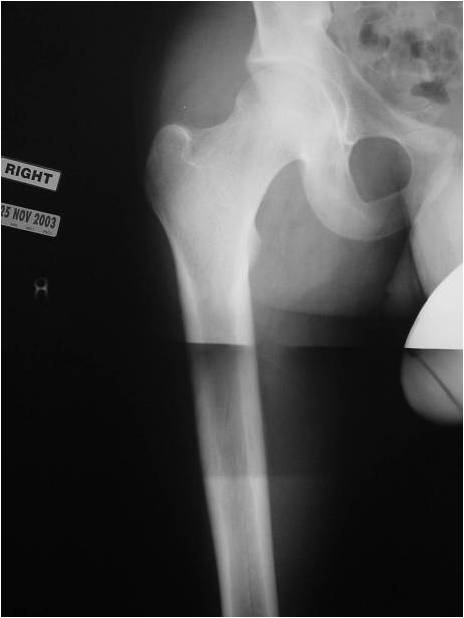

Sites:

- Most commonly arises from diaphysis but can also arise from metadiaphysis and metaphysis;

- Very rare epiphyseal involvement

- Long Bones – Most common

- Femur: Single most common site

Radiographic Presentation

- Permeative or moth eaten bone destruction

- Ill defined and malignant appearing

- Bony changes are often subtle

- Soft Tissue Mass in 90% of of cases

- Periosteal Reaction in 50% of cases

- Onion Skin (colic pattern of irritation)

- Hair on End (rapid continuous lifting of periosteum)

- Pathologic fracture in 10-15%